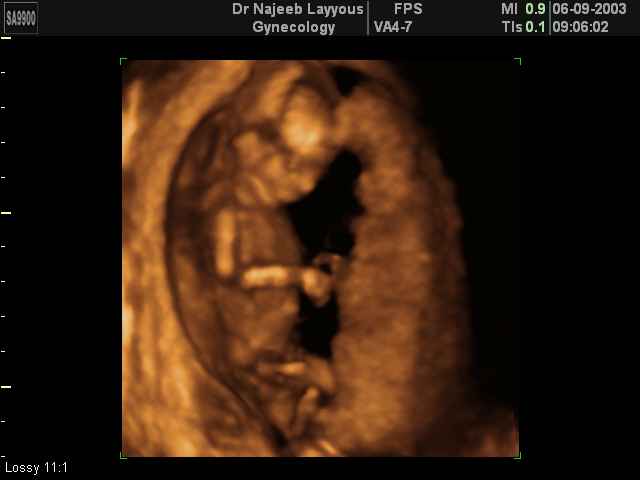

- Fetal Behavior Ultrasound Photos

Ultrasound Photos in 3D showing Fetal Behavior Inside the uterus | Dr N Layyous